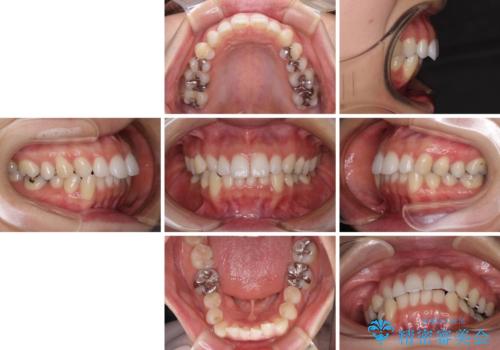

顎先に梅干し皺ができる 閉じにくい唇を抜歯矯正で閉じやすく

- 口元の突出感と口の閉じにくさを気にして来院された患者様です。

上下左右第一小臼歯4本を抜歯し、ワイヤー装置にて口元を引っ込めるよう矯正治療を行うこととしました。

奥歯が前方に傾斜していることで深く咬みこむ(ディープバイト)状態であったので、なかなか抜歯したスペースが閉じず、様々な方法でディープバイトを改善しながら治療を進めていくこととなりました。